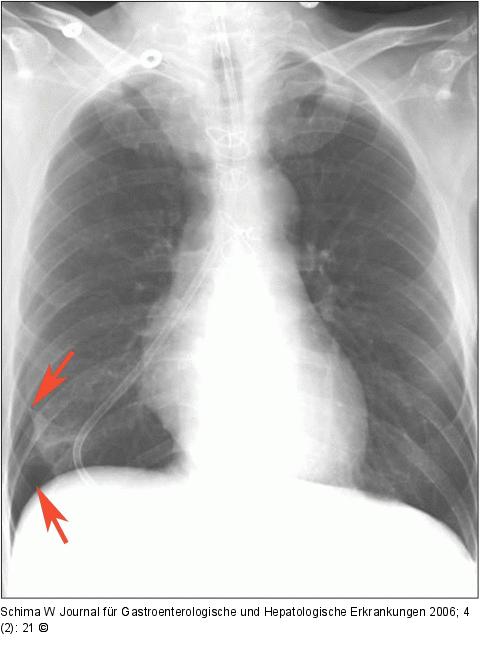

Abbildung 1: Magensonde - Fehllage Tracheobronchiale Fehllage der Magensonde mit der Spitze im Pleurasinus. Es besteht ein Pneumothorax rechts basal (Pfeile). |

Tracheobronchiale Fehllage der Magensonde mit der Spitze im Pleurasinus. Es besteht ein Pneumothorax rechts basal (Pfeile). |